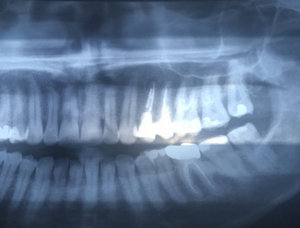

На каких зубах существует вероятность пульпита? 2. Есть ли вероятность, что на снимке присутствуют зубы, такие, что зуб значительно разрушен (от четырёх поверхностей), поэтому здесь требуется восстановление. То есть речь идёт о ситуации кариеса, когда пострадало более трёх поверхностей. Как известно, любой зуб имеет пять поверхностей (1. С внешней стороны. 2. С внутренней стороны (со стороны языка). 3. Со стороны левого соседнего зуба. 4. Со стороны правого соседнего зуба. 5. С жевательной стороны. Я понимаю, что точно диагноз нельзя поставить только по снимку, потому что нужен и визуальный осмотр, но речь идёт просто о возможности (подозрительных зубах и наиболее сложных).

Прям четких пульпитных явлений на снимке я не увидел. Шестой зуб сверху (26), требует установки коронки из-за большого количества пломбы, что по показаниям требуется реставрация вкладкой и коронкой. Не знаю про какой зуб идёт речь, но при разрушении коронковой части зуба более, чем на 50%, необходимо устанавливать коронки. Для более подробной консультации, обратитесь к стоматологу на очный приём.